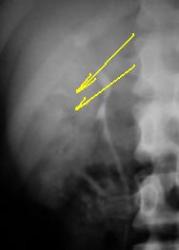

тот же больной томограмма позвоночника (боковой снимок вставлю потом):

Изображение

L1-L2 межпозвонковый диск и тело L2 вовлечены в процесс.

пациент из эндемичного по бруцеллезу района.

А мне кажется, что это обычная грыжа Шморля.

грыжа шморля 2х2 см?

Бывает, и именно в теле Л2. Во время призыва их любят называть б-нью Шоермана-Мау, которой в поясн. отделе не бывает в принципе. Если Вас смущает имя Шморля, назовите просто крупной интракорпоральной грыжей.

Изображениедобавляю боковой снимок.

Весьма интересная картинка. Деструкция?

Да, согласна, что это интракорпоральная грыжа Шморля(смотрите какой склерозик вокруг). А, что смущает?